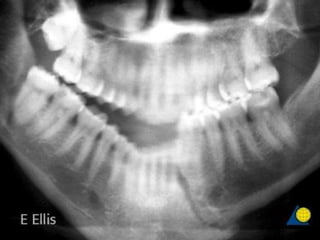

• #32 Panoramic x-ray taken 10 months postoperatively showing bone filling fracture gap